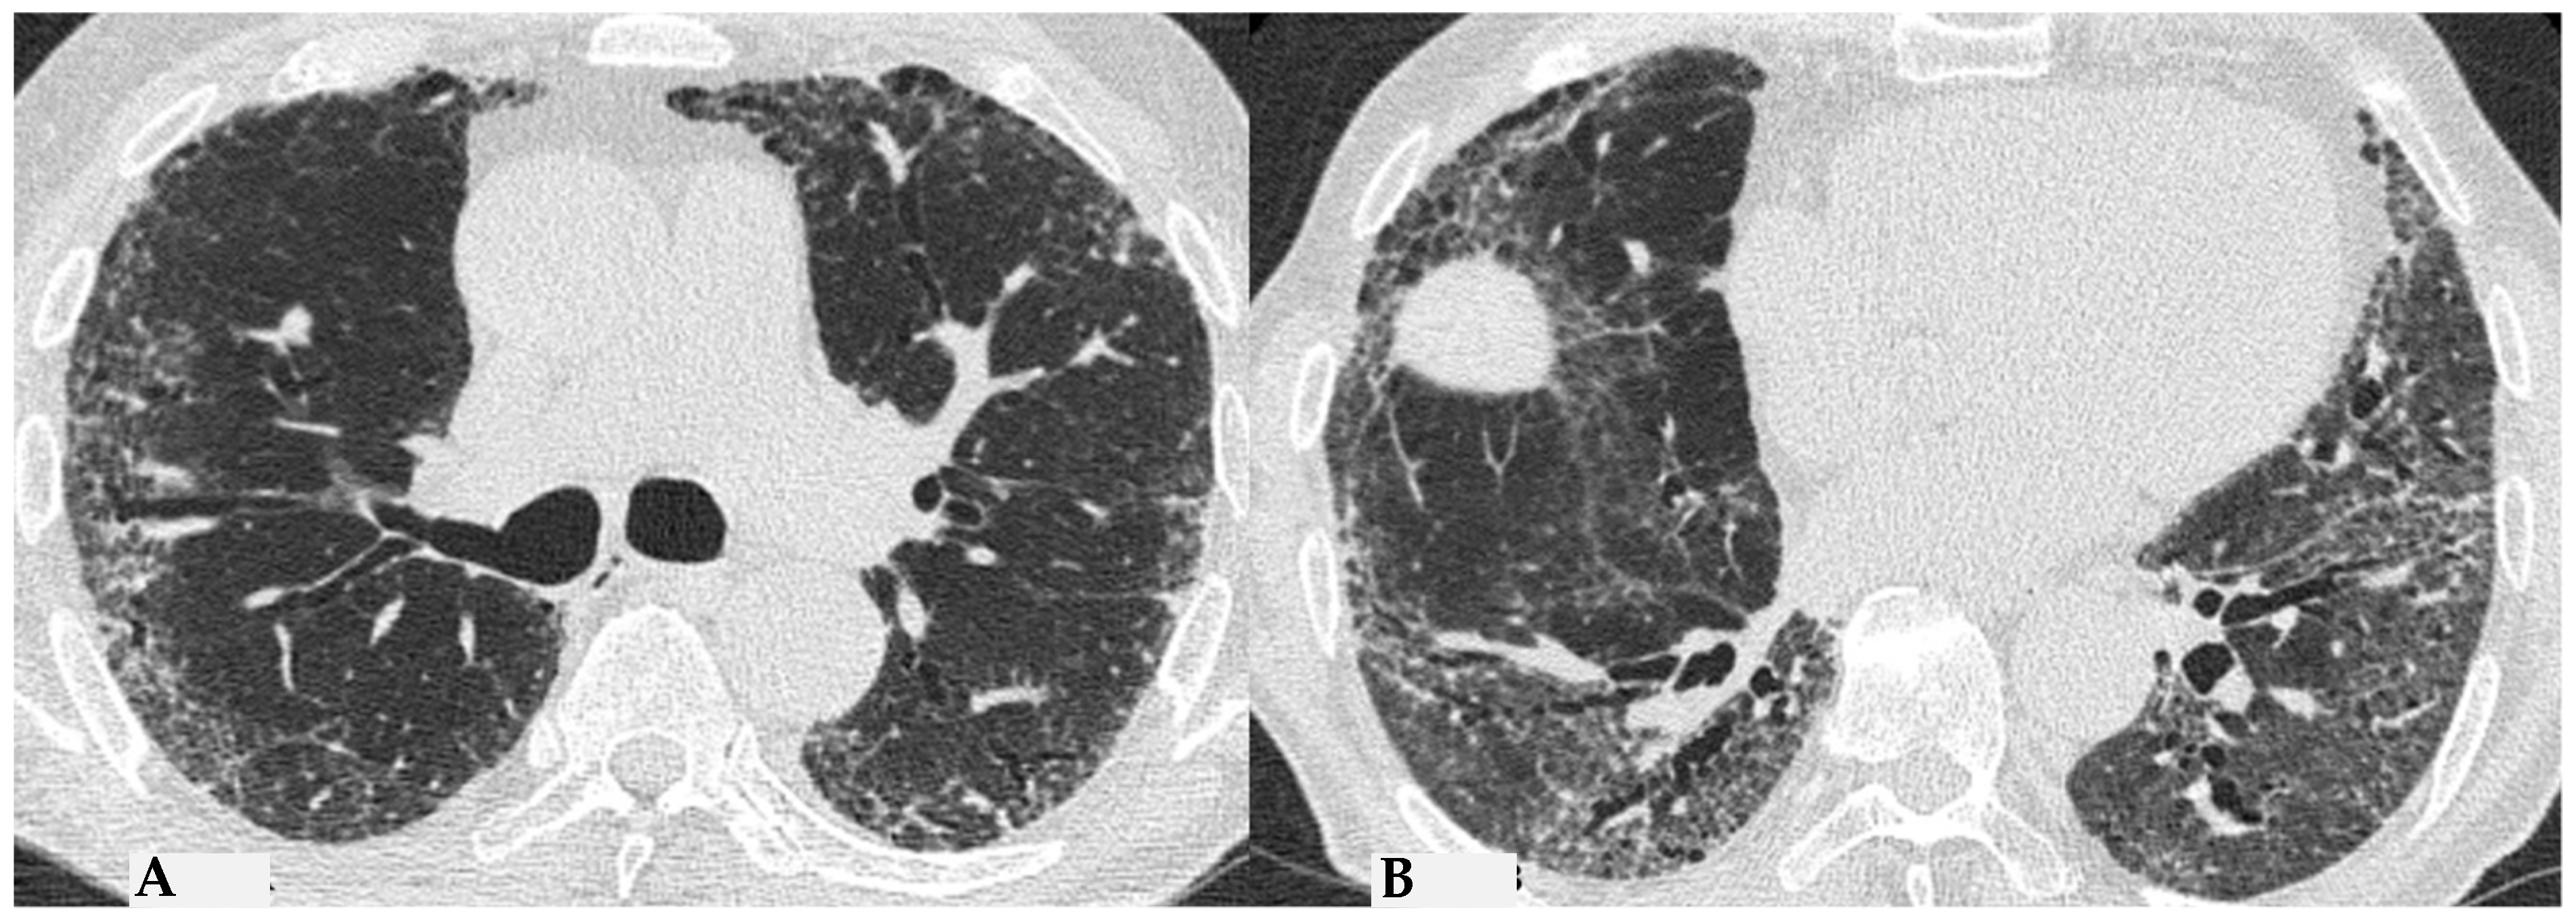

Figure 8.

Axial chest HRCT scan. Asymmetric fibrotic alterations with volume loss on the right in the upper lobe (A); in the lower lobes on the right, a significant extensive area of reduced attenuation is evident, suggestive of air trapping (red box), with components of distorted GGO and fibrosing characteristics with intra- and interlobular thickening and traction bronchiectasis/bronchiolectasis (B).

The absence of characteristic features of a “typical HP pattern” poses the “compatible with HP” pattern as a diagnostic challenge in distinguishing it from some other patterns, including NSIP and atypical forms of UIP/IPF. The clinical presentation can be insidious, characterized by an occasionally silent course, and likely correlated with the absence of a specific acute event of NFHP. Nevertheless, it exhibits non-specific clinical features analogous to other fibrotic ILDs, including dry cough and dyspnea, which may slowly lead to chronic respiratory failure like other idiopathic or secondary forms.

Semeiotic features classified as “indeterminate for FHP pattern” encompass the truly indeterminate HRCT pattern (Figure 9), fibrotic NSIP (Figure 10) and OP. Additionally, due to the primarily bronchocentric nature of the initial damage, the evolution of the fibrotic radiological features may reveal a characteristic centrifugal appearance in MPR reconstructions, with alterations in GGO/consolidative distortive fibrotic changes typically distributed centrally, sometimes sparing the subpleural anatomical surfaces. The patterns outlined in the latest international reference guidelines for HP result from a conclusive diagnostic multidisciplinary approach undertaken in the previous IPF guidelines of 2018 [10]. This correlation addresses the need to introduce a universal language, shared among specialists, that encompasses clinical, radiological and pathological aspects. This ensures the optimal finalization of a diagnostic-therapeutic process for better understanding and simplification [9,10,11]. HP is also coined “the great mimicker”, as it represents a deceptive disease from multiple perspectives; the presence of sometimes hidden antigens makes early diagnosis challenging. The disease course can be deceptive, resembling various pathologies. Without a comprehensive diagnostic panel, including thorough clinical and medical history evaluation, along with functional data and chest HRCT for pattern interpretation, untreated acute cases may progress to severe conditions. This includes the development of fibrotic ILD with end-stage terminal patterns, leading to a secondary but unfavorable outcome of pulmonary fibrosis. In addition to these respiratory complications, pulmonary arterial hypertension (PAH) may develop as a secondary condition to ILD, further compromising the patient’s prognosis. Therefore, it seems appropriate to integrate pneumological and radiological specialist examinations with cardiac evaluations, particularly echocardiography as an initial step, to obtain a diagnostic estimate of pulmonary arterial pressure. This information, in conjunction with complete clinical-functional-diagnostic data, is essential for the treatment of delicate and advanced forms of fibrotic HP with secondary PAH, especially considering the significantly different outcomes of patients with secondary PAH due to FHP [11,12,13,14,15,16].

Figure 9.

Truly indeterminate HP pattern. Chest HRCT, axial scan HRCT pattern characterized by mild fibrotic changes of a limited extent with patchy GGO in the upper lobes (A); the lower lobes show GGO, fine reticulations with modest mosaic attenuation and rare traction bronchiectasis/bronchiolectasis (B) with a “truly indeterminate” pattern according to new HP guidelines (2020) [4].

Figure 10.

f-NSIP pattern: chest HRCT, axial scan. Mild fibrotic changes of limited extent with a greater distribution in the upper lobes with superimposed GGO (A); the lower lobes show marked extension of GGO, fine reticulations with traction bronchiectasis/bronchiolectasis (B); “fibrotic NSIP pattern” according to new HP guidelines (2020) [4].